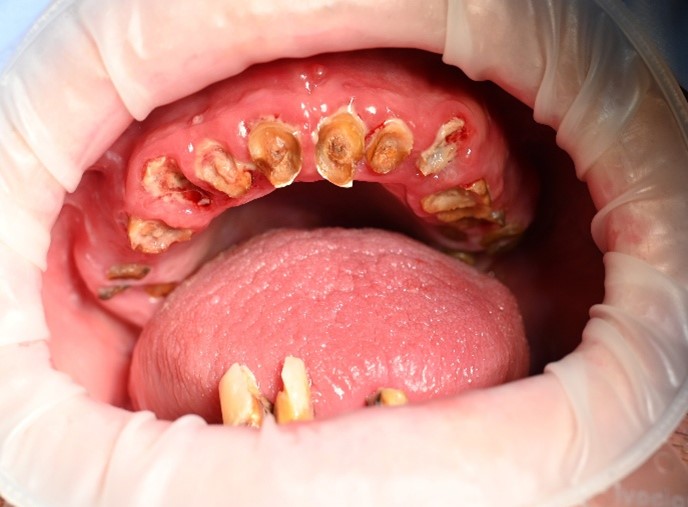

Full Arch All-On-X Dental Implants - Before

BEFORE

This patient presented with significant dental concerns affecting both oral function and smile appearance. Everyday activities such as eating, speaking, and smiling comfortably had become increasingly difficult.

Like many people exploring full mouth dental implants, the patient was seeking a fixed and reliable solution that could restore both confidence and quality of life.

The patient visited Sayers Dental feeling frustrated with his remaining broken teeth and was ready for a fresh start. He wanted to eat comfortably, improve his appearance, and regain the confidence to smile again.